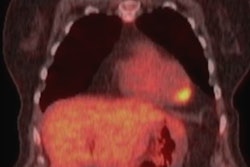

A hot topic at the recent congress of the European Society of Cardiovascular Radiology was cardiac FDG uptake in PET/CT. A team from Turkey and the U.K. has looked closely at this controversial subject, and the findings are worth a read. You can do so in our MRI Community, or by clicking here.